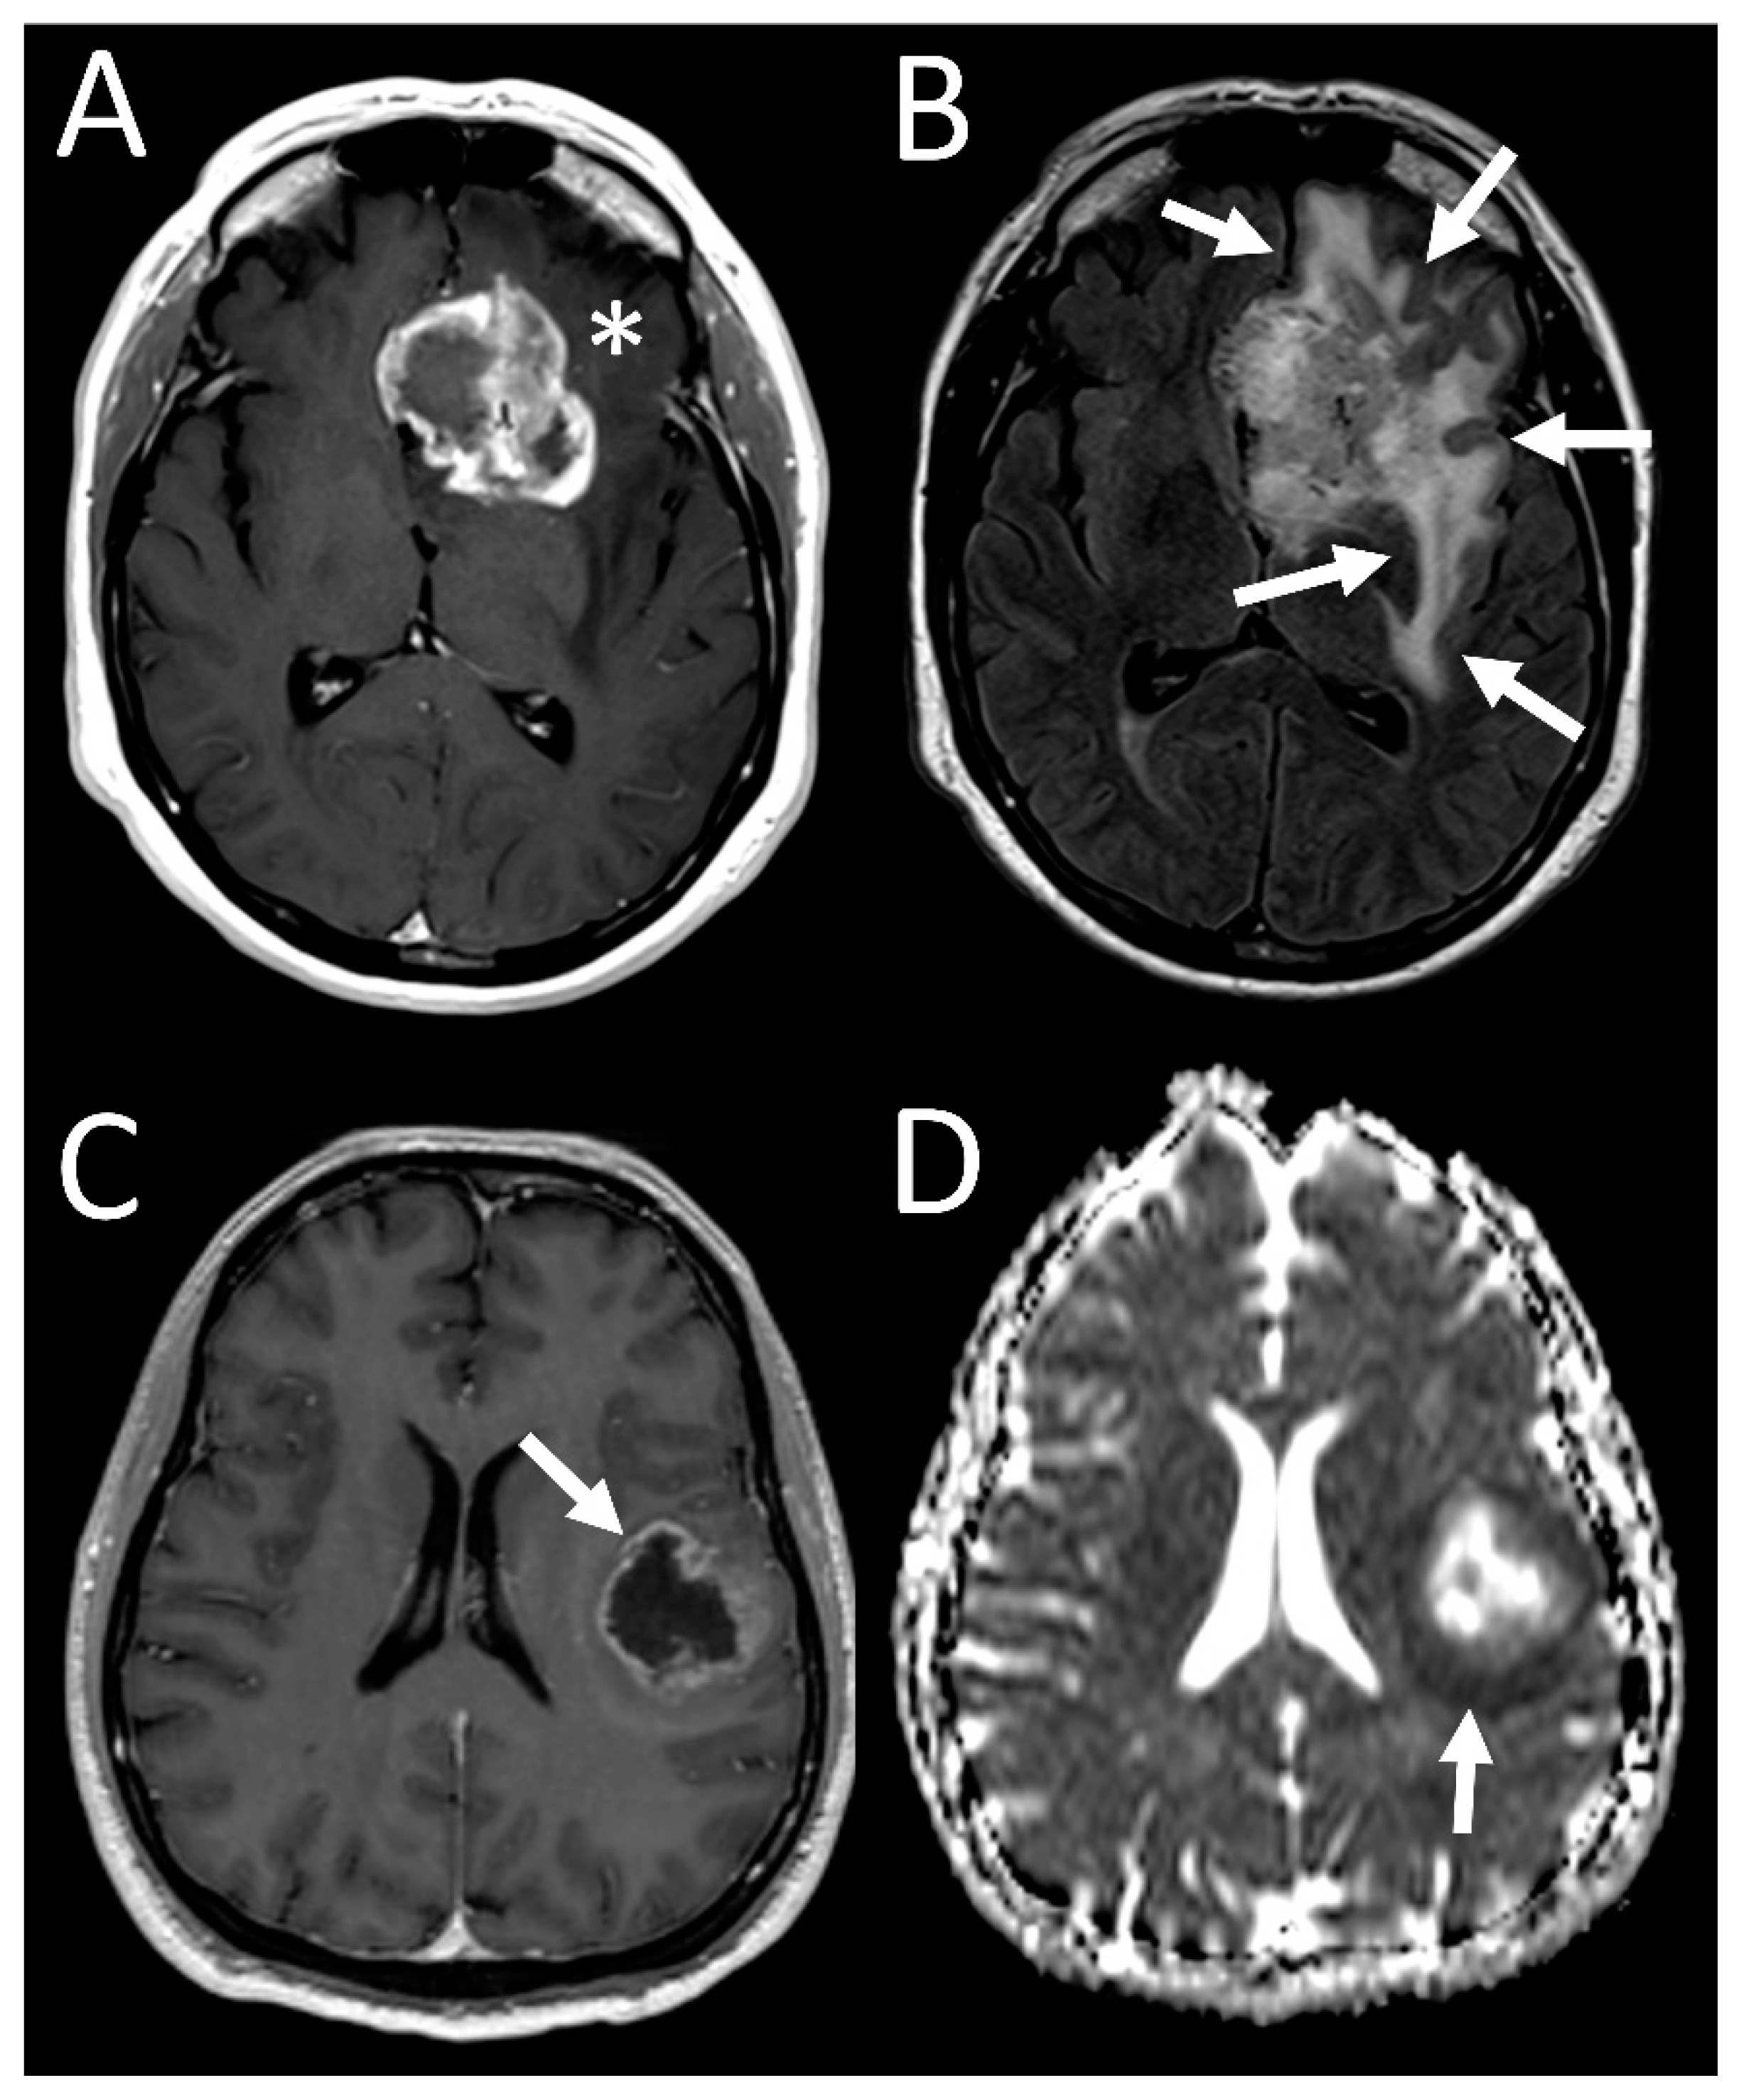

Figure 1.

Sample imaging features of glioblastoma with 19/20 co-gain. (A) T1 postcontrast image of left frontal tumor demonstrating avid enhancement (asterisk), with (B) FLAIR image showing a large area of surrounding edema (arrows). (C) T1 postcontrast image of another tumor shows thinner rim of enhancing tumor (arrow), with (D) ADC map showing an area of non-enhancing, diffusion-restricting tumor beyond the enhancing tumor (arrow).